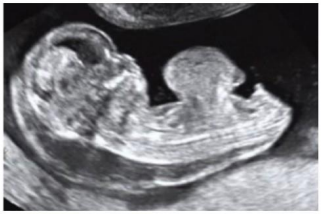

Uma paciente de 16 anos de idade, G1, realizou ultrassonografia morfológica de primeiro trimestre, na qual foi detectado um defeito de parede abdominal central ventral no feto, como mostra a imagem a seguir.

Para esse caso clínico, o diagnóstico fetal é

onfalocele.